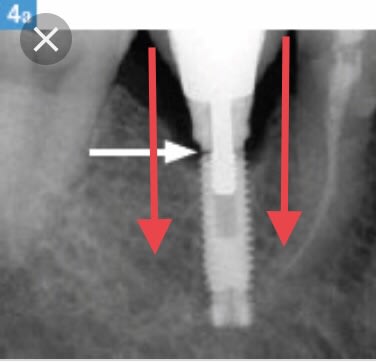

Allez parce que je suis sympa avec vous :) je vous mets une petite radio .

Un joli petit implant sur lequel on a crû bon de mettre une belle molaire. Le problème c’est que les forces en rouges ont peu à peu entraînées des complications. Beaucoup de surplomb, portions de la couronne qui repose dans le vide. Mouvement de balancier droite gauche droite gauche etc etc avant arrière avant arrière.... Forcément au bout d’un moment ça se dévisse et ça casse.